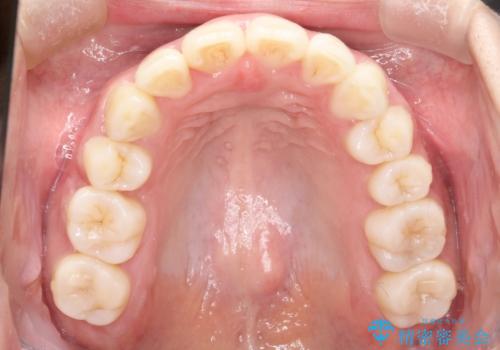

- 上の前歯が出てて、前歯で咬めないとのことで来院されました。

上顎の歯を1本抜歯して、前歯のガタガタと、前方に出ているのを改善する計画としました。

上下の前歯の距離が近くなり、前歯で咬みやすくなり、審美的にも改善できました。